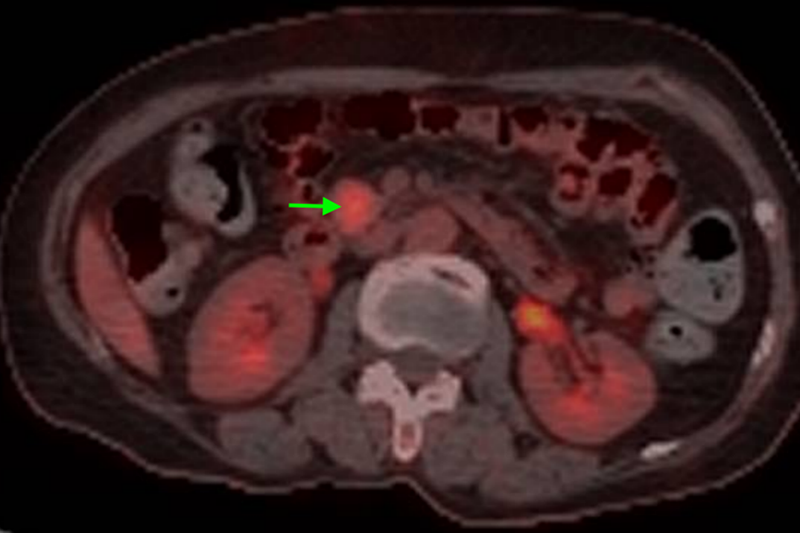

經(jīng)檢查,陳大嬸有低血糖癥狀、代謝性腦病,進(jìn)一步行PET/CT檢查及腹部增強(qiáng)CT檢查后考慮為胰島素瘤。內(nèi)分泌科立即組織肝膽胰外科、神經(jīng)內(nèi)科、內(nèi)分泌科、臨床營(yíng)養(yǎng)科、麻醉科等多學(xué)科聯(lián)合診療,專家們討論后一致認(rèn)為陳大嬸的胰島素瘤有明確手術(shù)指征,于是轉(zhuǎn)入肝膽胰外科進(jìn)一步手術(shù)治療——腹腔鏡探查、胰腺鉤突腫瘤切除術(shù)。

專家團(tuán)隊(duì)進(jìn)行了精心的術(shù)前準(zhǔn)備,并制定了精細(xì)化麻醉方案。術(shù)中,肝膽胰腺外科手術(shù)團(tuán)隊(duì)參考術(shù)前CT資料及術(shù)中腔鏡超聲精確定位腫瘤,將胰島素瘤完整切除,整個(gè)手術(shù)過程時(shí)間僅為80分鐘,出血量?jī)H為5ml。術(shù)后,患者血糖水平恢復(fù)到正常水平,認(rèn)知障礙逐步得到改善,一周后復(fù)查CT未見胰漏。出院前,陳大嬸體力、飲食、精神等方面完全恢復(fù)正常,已能和家人順利交流,終于擺脫了被誤解的慘痛經(jīng)歷。